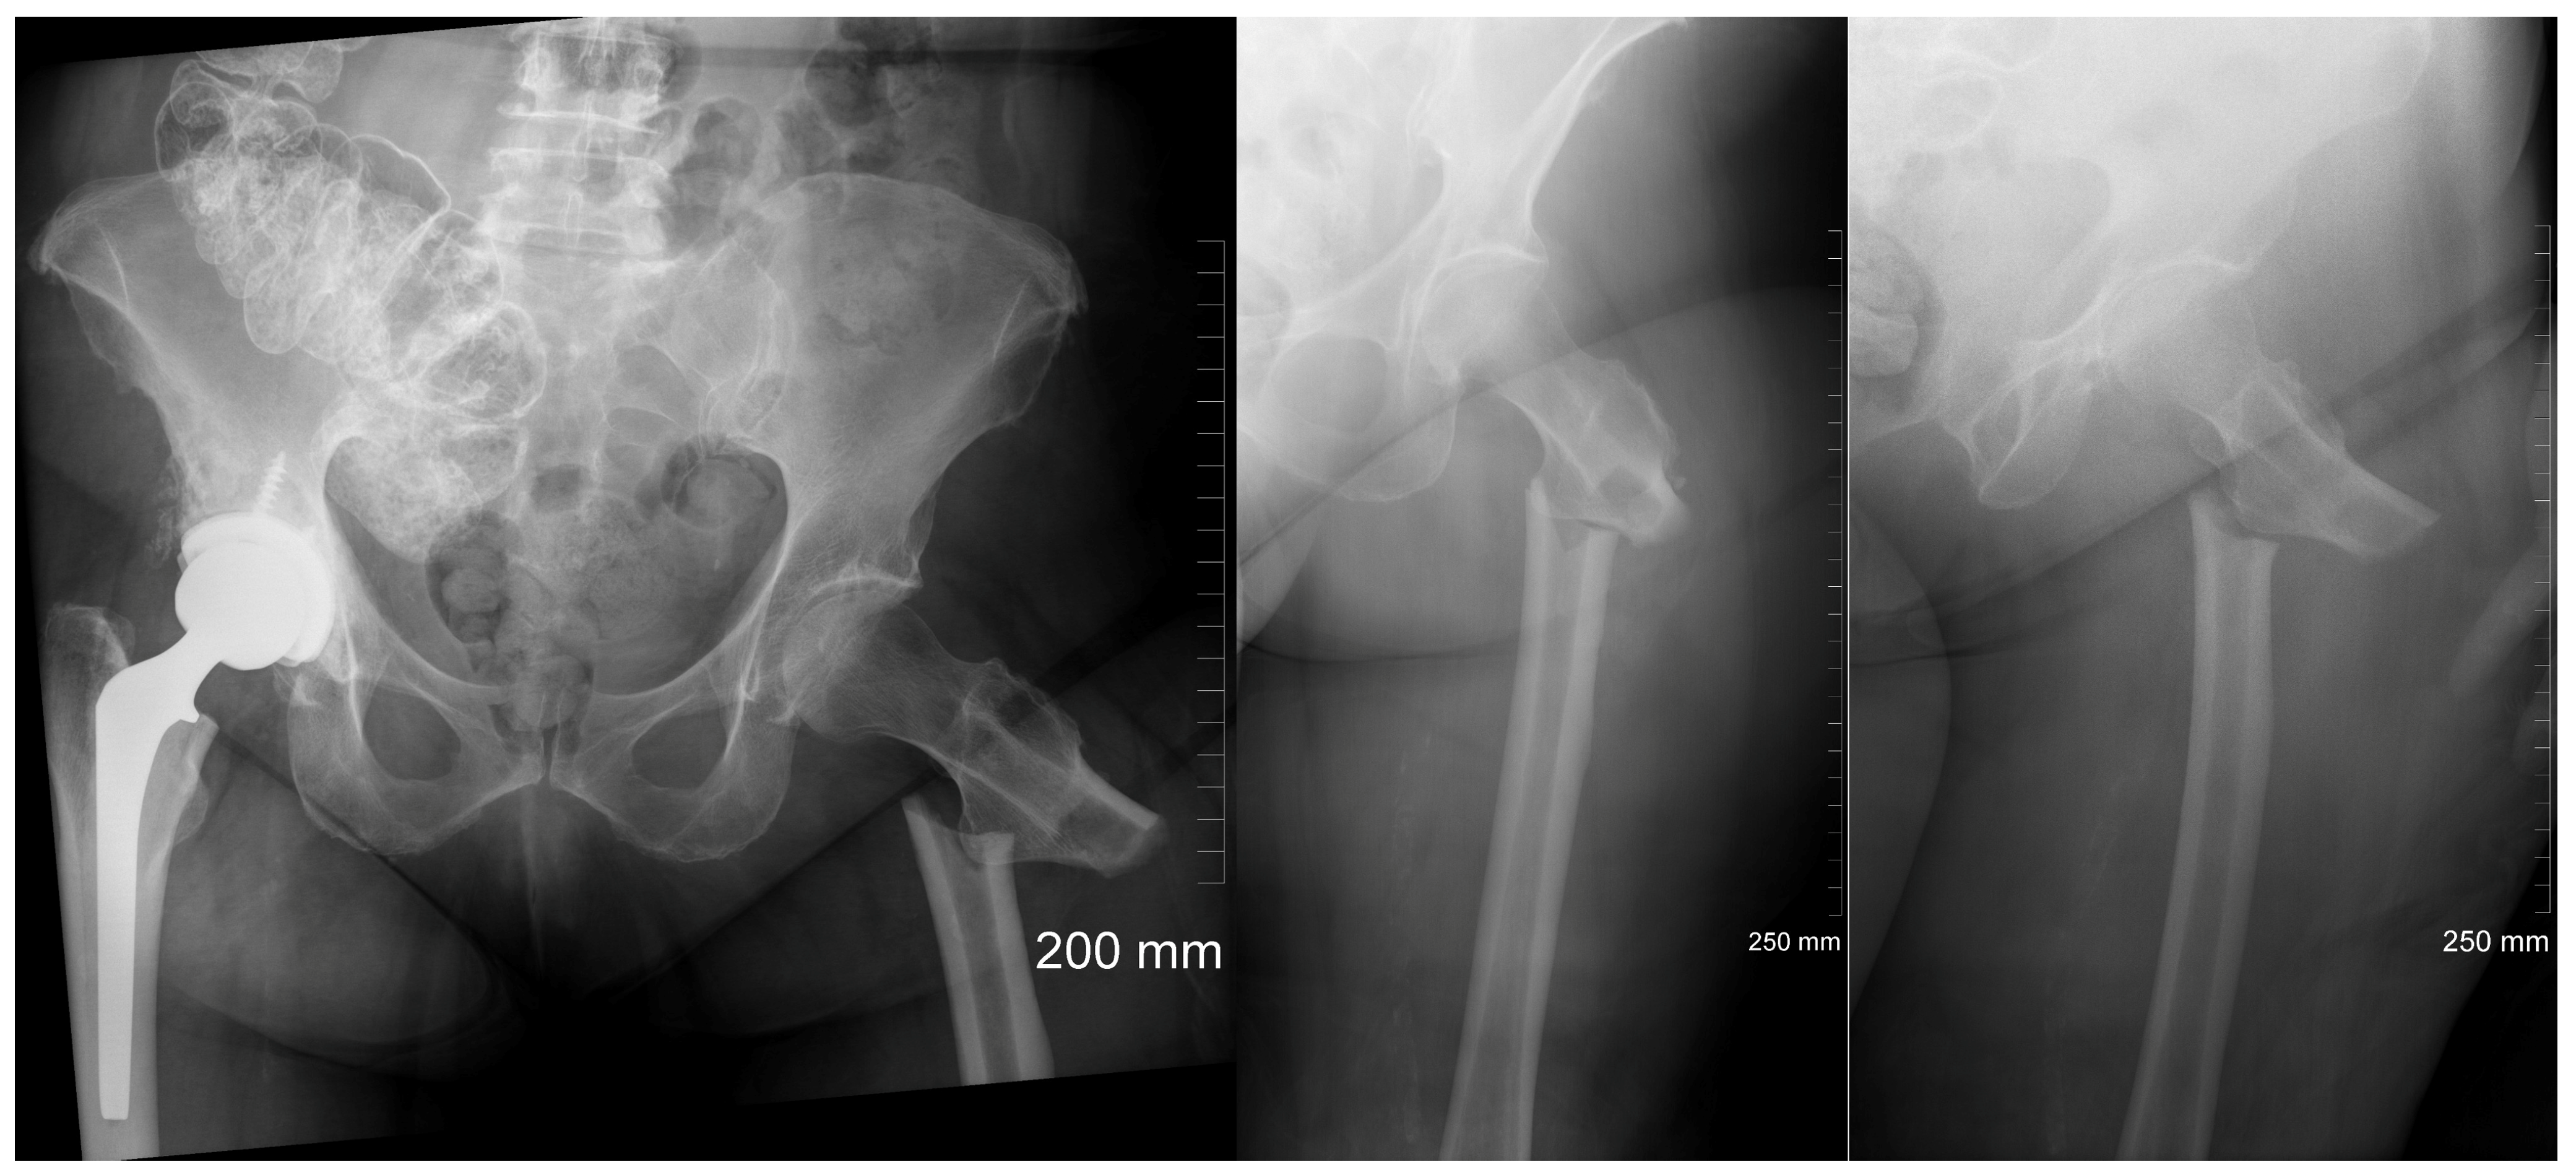

2. Case Description